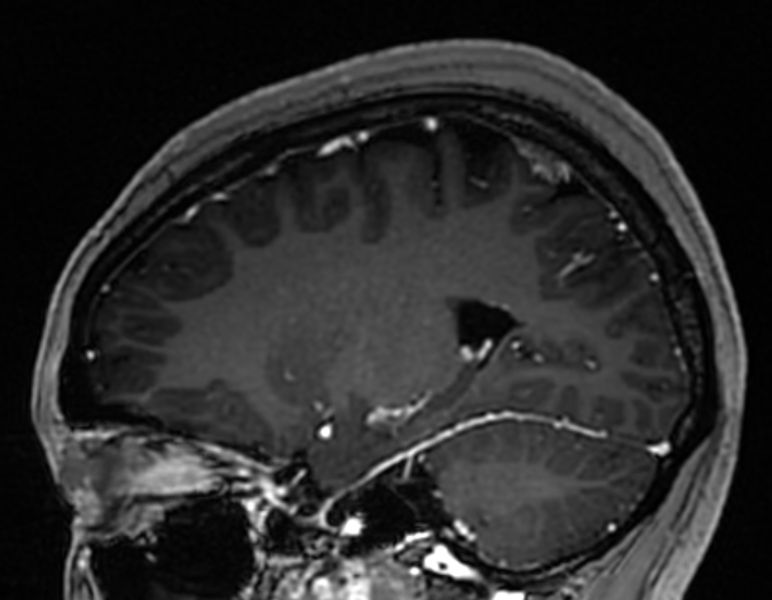

入院后,医院为她进行了详尽的颅脑MRI增强及头颅CT薄扫检查,结果显示其病变位于左侧顶上小叶,病变对脑组织压迫明显(病变周围脑组织CBF灌注明显降低、较对侧脑回体积明显减小),且与左侧大脑上静脉紧密相关,动态视频脑电图分析进一步提示病灶周围脑组织存在异常放电。

术前MRI矢状位图像

术前MRI提示左侧中央后回较对侧稍小。